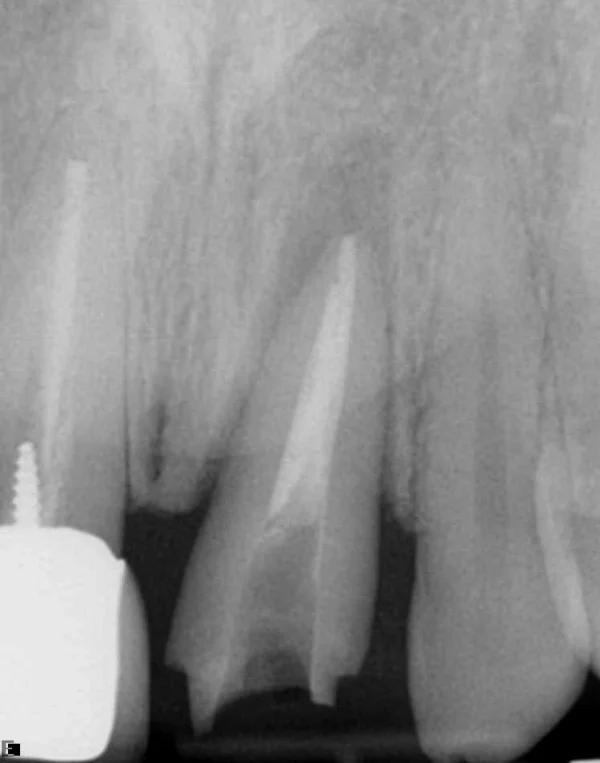

Surgical repositioning of teeth

Initial clinical presentation with CC of "Can you cement back my tooth?"

Removed post and surgically repositioned for 2 mm ferrule